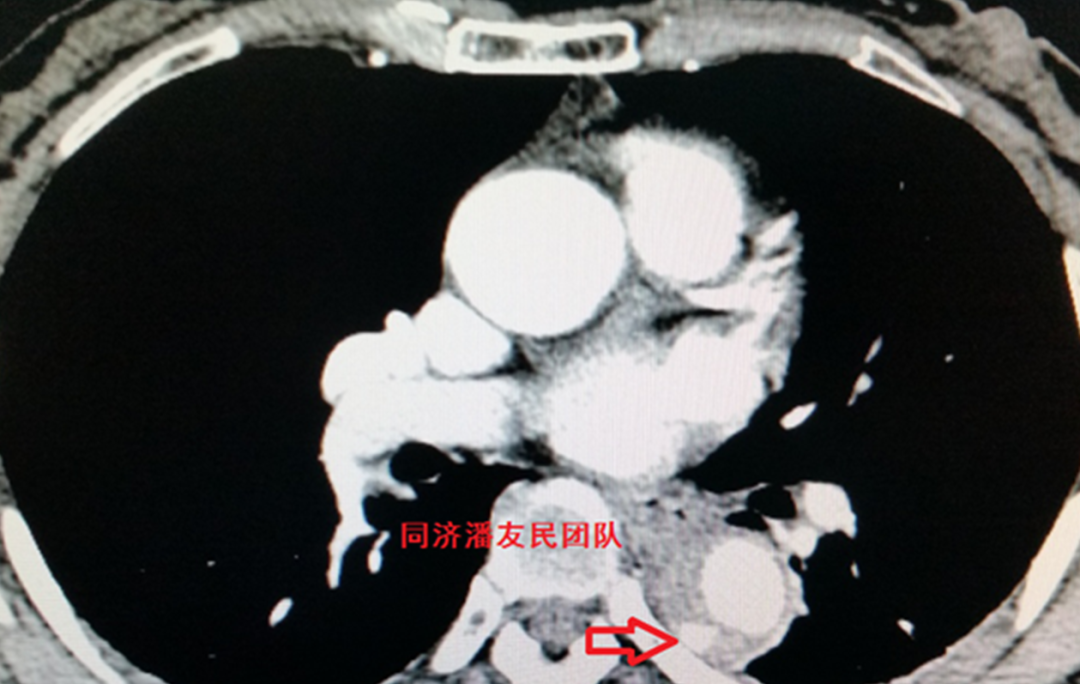

除了主动脉病变外,通常还合并其它系统损伤:如胸腔积液、气胸、肋骨骨折、肝脏破裂出血等多器官损伤情况(图7、8)。

图7 红箭头显示外伤性主动脉夹层,红星号显示双侧胸腔积液

图8 红箭头显示外伤性腹主动脉夹层,红星号显示肝脾包膜下破裂出血。